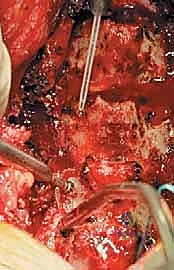

تُجرى عملية رأب الصفيحة العنقية تحت التخدير العام، وتستغرق عادةً ما بين ساعتين إلى أربع ساعات، اعتماداً على عدد المستويات الفقرية المتأثرة. يتبع الأستاذ الدكتور محمد هطيف بروتوكولاً جراحياً دقيقاً وصارماً لضمان أعلى نسب النجاح.

الخطوة 2: الشق الجراحي والوصول للعظام

يُجري الدكتور هطيف شقاً جراحياً دقيقاً في منتصف الجزء الخلفي من الرقبة. يتم إبعاد عضلات الرقبة الخلفية برفق ولطف شديدين للوصول إلى الصفيحات العظمية (Laminae) للفقرات المستهدفة (غالباً من C3 إلى C6 أو C7).

الخطوة 3: إنشاء "المفصلة" (The Hinge)

باستخدام مثقاب جراحي دقيق (High-speed Burr) تحت التكبير الميكروسكوبي، يقوم الدكتور هطيف بنحت أخدود طولي على جانب واحد من الصفيحات العظمية (عند نقطة التقاء الصفيحة بالكتلة الجانبية). هذا